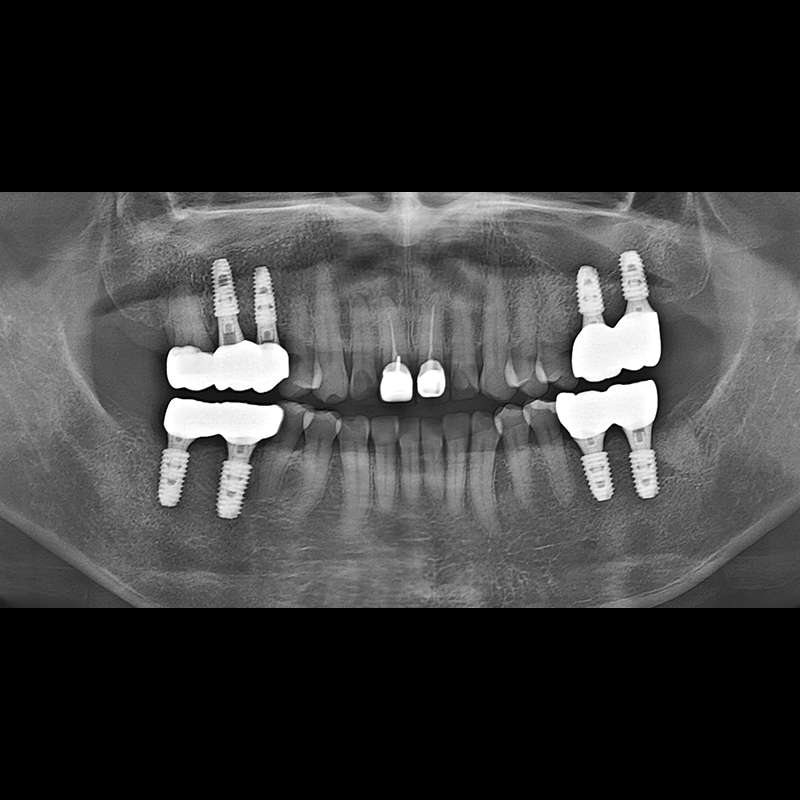

インプラント手術事例 2025.05.30

欠損した歯の部分と、生かしにくい歯の位置にインプラントを植立しました。